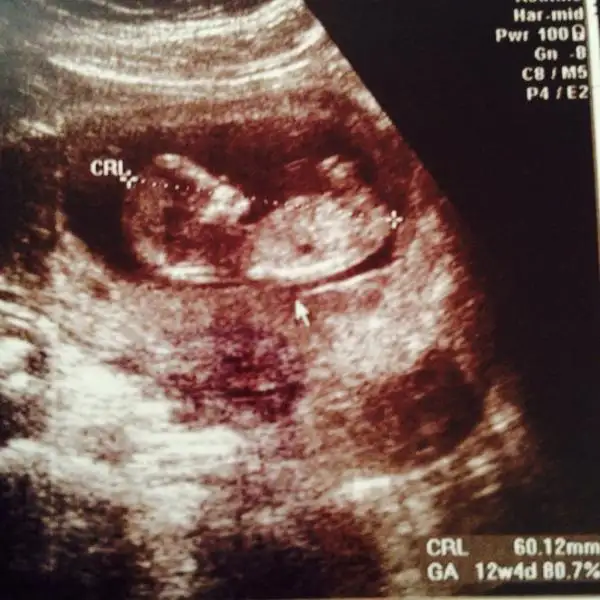

Eki Görüntüle 1211261 hocam benim için de bir bakar mısınız? 12 hafta 6 gunluk sonucumuz ... doktor bir şe demedi erken dedi...

Nubunu görüyorum kendimce ama senin bebise emin olarak demiyorum çünkü nubun üstü de karisik canim bence kiz gibi hayirlisi saglikla kucaginda olsun güzel hamilelikleri geçirin bugunlerinizi iyi degerlendirimln